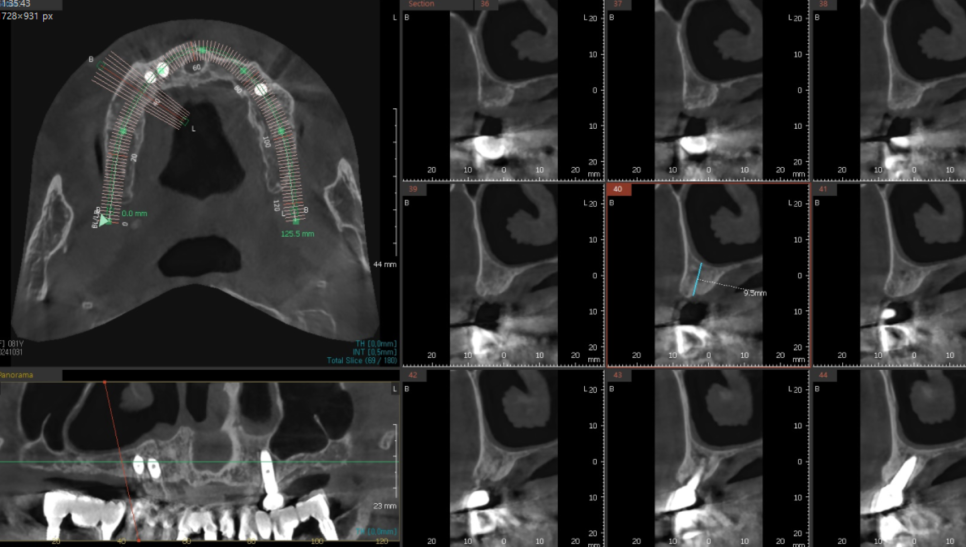

241129

임플란트는 연령에 상관없는

뼈만 있으면 할 수 있다는 것을

ct를 통하여 보여드리고

환자분이 가지고 있는 두가지 문제

위, 아래 치아와의 궁합 관계를 고려하여

임플란트가 적절함을 설명드렸죠.